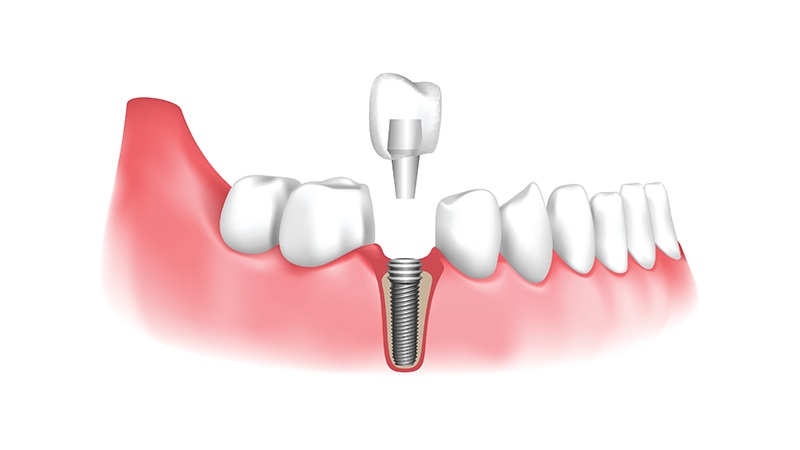

- ایمپلنت دندان اصفهان

روشهای نوین در رفع عفونت و التهاب اطراف ایمپلنتهای دندانی

روشهای نوین در رفع عفونت و التهاب اطراف ایمپلنتهای دندانی: از پری ایمپلنتیت تا مدیریت بالینی

پری ایمپلنتیت، بهعنوان یکی از چالشهای م...